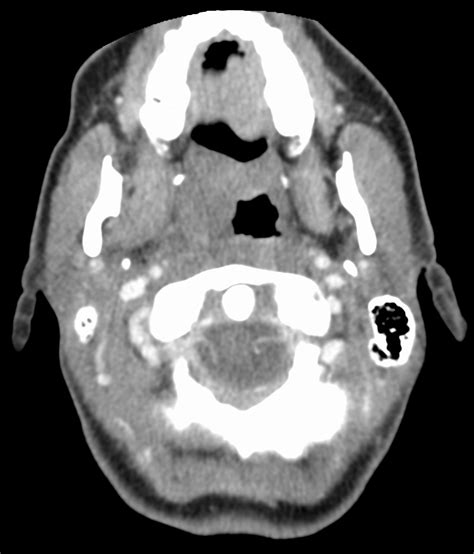

CT coronary angiography , or CCTA, is a non-invasive imaging test that uses computed tomography (CT) scans to create detailed pictures of the coronary arteries. These arteries are responsible for supplying blood, oxygen, and nutrients to your heart muscle. The process involves a CT scanner, which is a large machine that uses X-rays to generate cross-sectional images of your body. The images are then reconstructed to create a 3D view of your coronary arteries, revealing any blockages, narrowing, or other abnormalities.

Now, let’s talk about IV contrast . During many CCTA scans, a contrast agent, usually containing iodine, is injected into a vein in your arm. This contrast agent helps to enhance the images, making the coronary arteries more visible. Think of it like adding dye to a river; it helps to highlight the flow and any obstructions. The contrast agent temporarily increases the density of the blood in the arteries, allowing the CT scanner to better visualize their structure and identify any blockages. Without contrast, it can be more challenging to differentiate the arteries from the surrounding tissues.